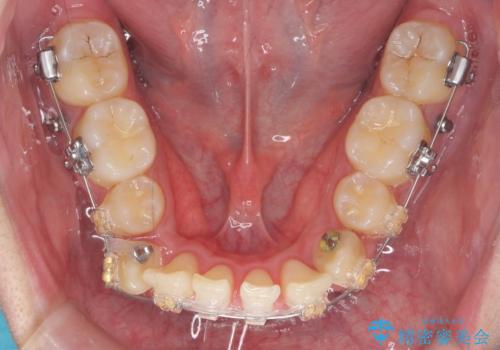

上下左右の小臼歯を抜歯しています。

下のがたつきが大きいため、抜いたスペースをしっかり利用して並べるため矯正用インプラントを使用しています。

上下の前歯の重なりが大きく(過蓋咬合)時間がかかりましたが、しっかり浅く仕上げることができました。